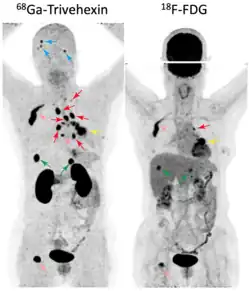

A prospective clinical study (NCT05835570)[38] involving 58 participants with non-small cell lung cancer (NSCLC) compared the diagnostic performance of 68Ga-Trivehexin PET/CT with 18F-FDG PET/CT.[37] Both radiotracers showed similar diagnostic accuracy (100%, 58/58) for the detection of primary tumors. The sensitivity for detection of lymph node metastases was comparable for 68Ga-Trivehexin (80%) and 18F-FDG (72%), but 68Ga-Trivehexin showed a higher specificity (93.8%) and accuracy (91.2%) than 18F-FDG (62.5% and 64.2%, respectively). Sensitivity for detecting brain metastasis was 92.3% for 68Ga-Trivehexin and 38.5% for 18F-FDG, mainly because of the high glucose consumption of normal brain tissue, which usually results in a high physiological uptake of 18F-FDG in the brain, generating a strong background signal which frequently obscures brain metastases in PET images (see image).

Head-and-neck cancer

In a cohort of 20 suspected (19 confirmed) head-and-neck squamous cell carcinoma (HNSCC) cases, 68Ga-Trivehexin PET had a higher sensitivity (92.5%), positive predictive value (PPV, 100%), and accuracy (93%) than the standard 18F-FDG PET, for which sensitivity, PPV, and accuracy were 90%, 93.1%, and 84.3%, respectively.[32] 68Ga-Trivehexin was furthermore applied in a case of tonsillar carcinoma metastasized to the brain (see image).[31]